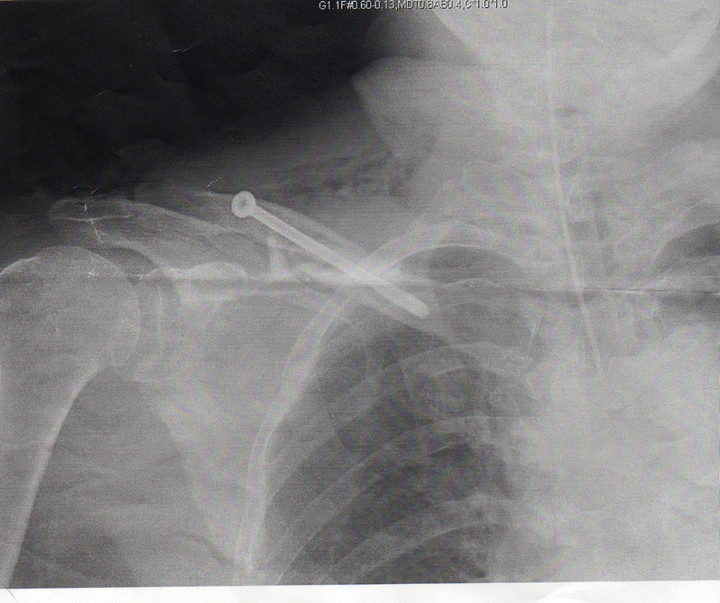

医師「右鎖骨、見事に折れてますね・・・」

医師「上の方法だと傷口が小さくて済みます、下の方法は切開を大きめにします」

7日現在三角筋で右手をだいじそうに抱えております。